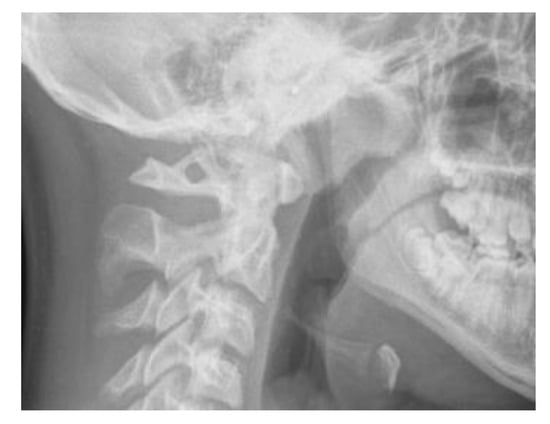

The sella turcica and pterygopalatine fissure morphologies were analysed by evaluating the measurements according to the criteria by Axelsson et al. [16]: the width/length was considered as the measurement from the tip of the dorsum and the tuberculum while the height/depth of sella and pterygopalatine fissure was a perpendicular line to w-line to the deepest point on the floor of the sella or pterygopalatine fissure. The ratio between h-line and w-line of both anatomical parts was measured (Figure 4).

Figure 4. Sella Turcica (a) and pterygopalatine fissure morphology analysis (b). Reference lines: h-line (height/depth) and w-line (width/length).